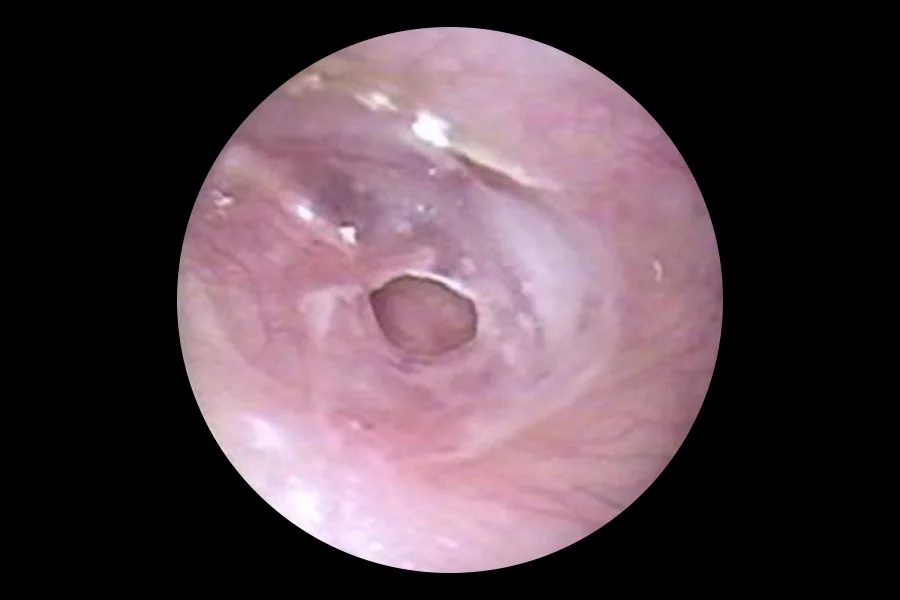

Repair of the ear drum and hearing bones is termed tympanoplasty. This may be done either via the microscopic or endoscopic technique depending on certain factors. Both techniques are done by us.